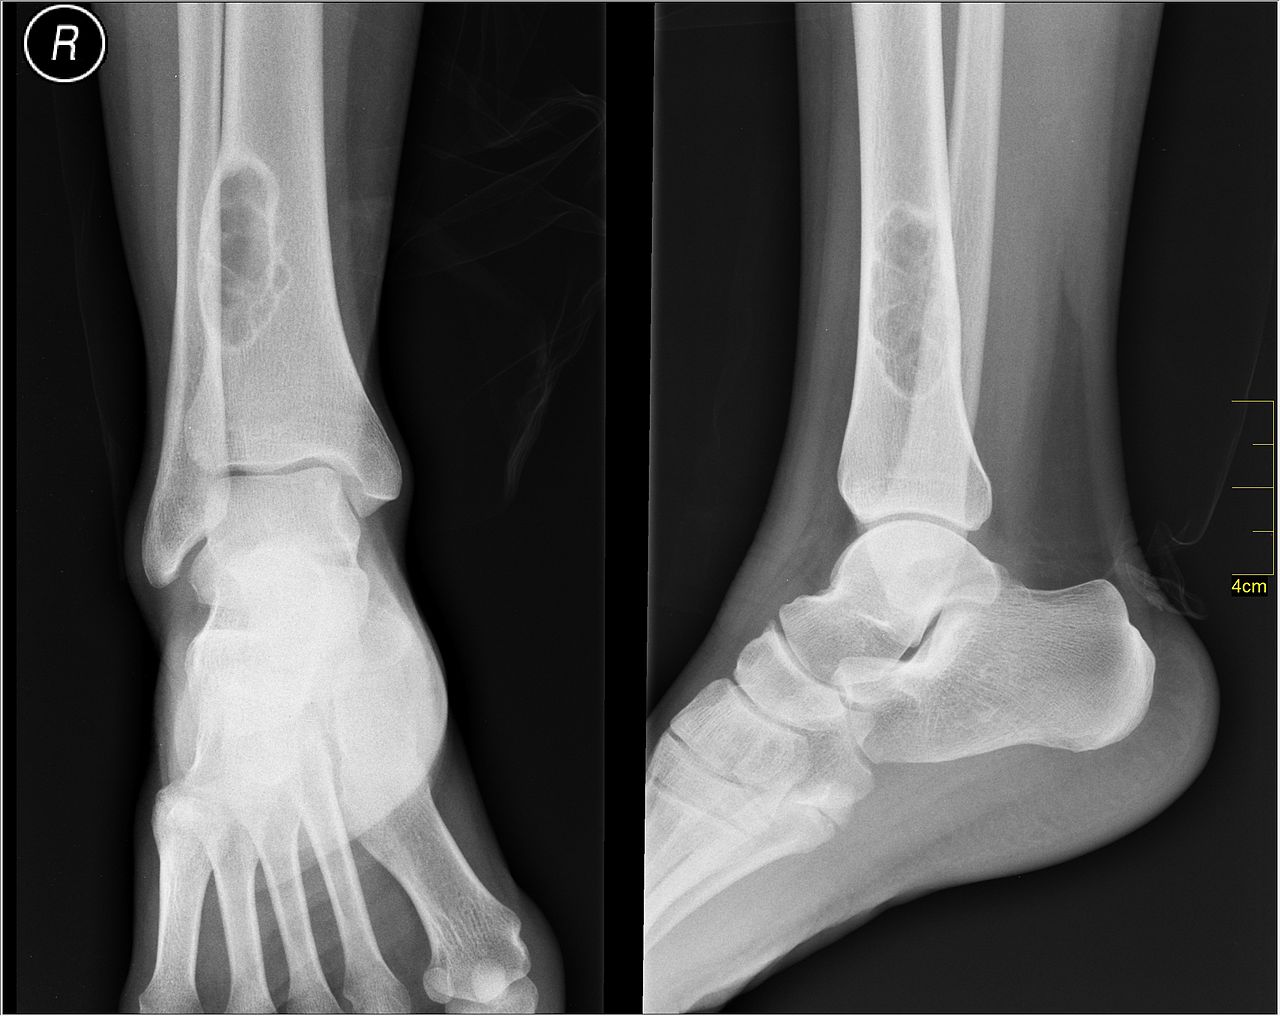

After querying their availability so many times, I eventually got a doctor to show me my x-rays/let me take pictures on my phone. They’re as impressive as expected!

I’m not really an expert on anatomy in the slightest, so can’t really provide much information beyond what the doctor told me (which I was a bit out of it on morphine still)! I think that the above pic is taken from the side. The main point to take away is that the foot is supposed to be under the leg bones. I’m told that the lumpy bit at the top to the left of the leg bones is the chunk that I had sheared off of the bone. The bone bits (technical term I’m sure) below this are supposed to be under the leg bones. I was pretty out of it that night and can’t really remember the timeline of events, but I assume that this one is before they put the ankle back in the joint. The ankle was manipulated a bit before this to at least be facing the correct direction, but I can’t say when that had happened! My friend accompanying me to the hospital kindly took photographs of me during the ordeal, and took this one of me before the ankle was put back in, but it appears to be in vaguely the correct direction.

This x-ray seems to show pretty well how wrecked the joint was! The lump on the top of the leg bones is the chunk that I had broken off, you can kind of see where in the darker patch under it. Honestly, it’s quite hard for me to interpret these images- they look so different to how a normal ankle x-ray does, it’s difficult! I’m going based on the leg bones, as they seem to be fairly intact. The toe position doesn’t really seem to be sufficient for working out orientations, as the foot has been rotated a bit oddly!

This picture from Wikipedia shows an ankle joint (albeit one that appears to have a tumor above it), and I think that my above x-ray picture is taken from a similar angle to the one on the right: